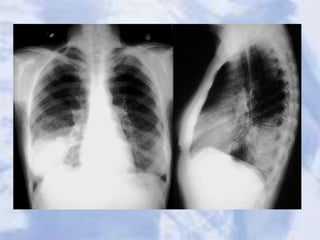

Case 20

Widened Mediastinum: Aortic Dissection

Pulmonary artery stenosis with cardiomegally likely

secondary to stenosis.